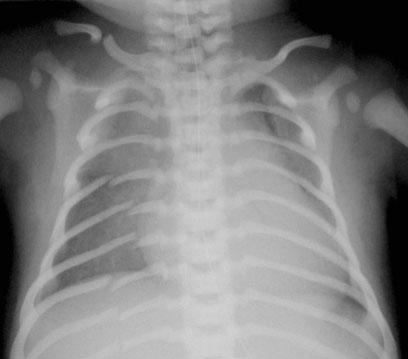

Chấn thương sản khoa do cân nặng lúc sinh cao và cuộc sinh khó đã được đề xuất là nguyên nhân gây gãy xương sườn ở trẻ nhũ nhi, tuy nhiên điều này cực kỳ hiếm gặp (xem hình).

Gãy xương sườn liên quan đến chấn thương do tai nạn rất hiếm gặp và đòi hỏi một lực tác động đáng kể, chẳng hạn như chấn thương trực tiếp vào thành ngực trong tai nạn giao thông, bởi vì thành ngực đàn hồi và linh hoạt hơn của trẻ nhũ nhi cho phép chịu đựng lực nén lớn hơn mà không bị tổn thương.

Hồi sức tim phổi (CPR) cũng đã được cho là nguyên nhân gây gãy xương sườn. Tuy nhiên, nhiều trẻ bệnh nặng được thực hiện CPR mà không có bằng chứng gãy xương sườn. Quan trọng hơn, CPR chưa được ghi nhận là nguyên nhân gây gãy xương sườn phía sau.